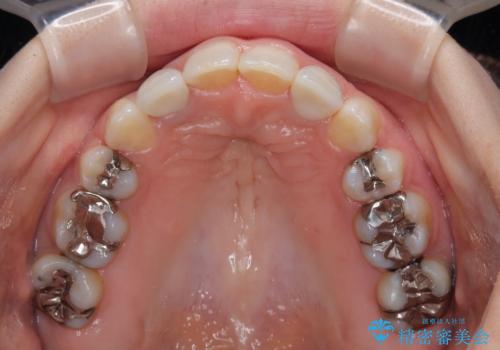

- 上顎前歯が叢生により前方に出ている状態や、全体的なむし歯を気にして来院された患者様です。

全体的にむし歯や欠損が多く、矯正治療とは別に処置が多く必要な口腔内でした。

目立たないハーフリンガル矯正を希望され、裏側装置はどうしても清掃性が低下し、むし歯発生のリスクが高まるため、矯正治療前にしっかりとむし歯治療を行い、矯正治療後にセラミックによる補綴治療を行うこととしました。